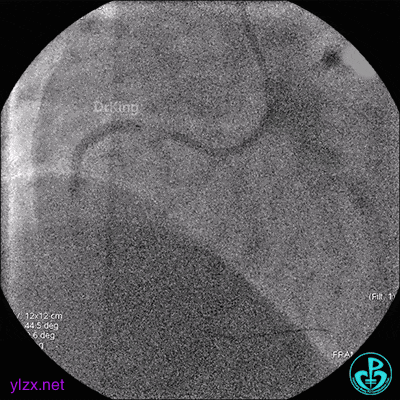

6 二次治疗

1周后复查造影,见粗大前降支3级血流,近端严重狭窄伴管壁严重钙化影,病变累及前降支开口。

最后造影结果显示前降支3级血流,支架膨胀尚可。